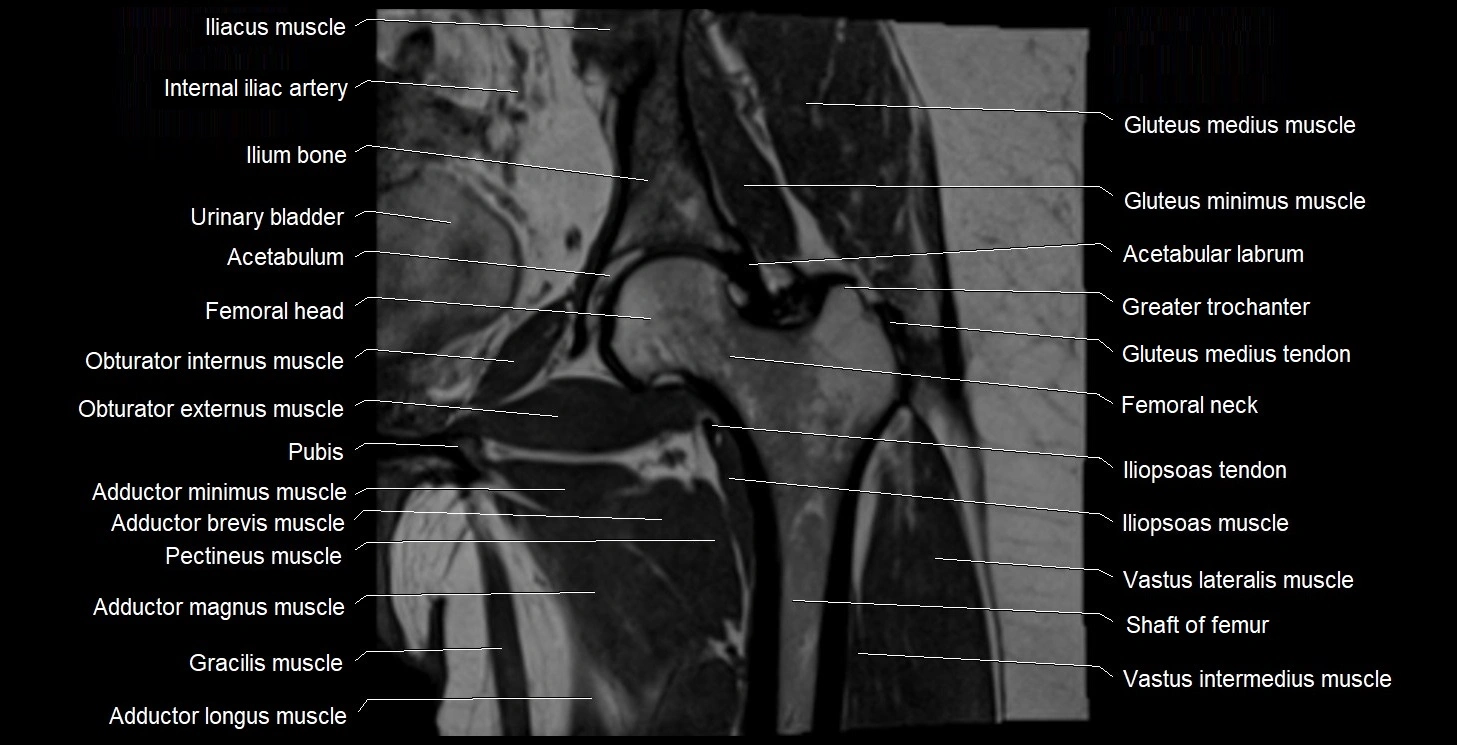

- Acetabulum

- Adductor brevis muscle

- Adductor longus muscle

- Adductor magnus muscle

- Adductor minimus muscle

- Gluteus medius muscle

- Gluteus medius tendon

- Gluteus minimus muscle

- Gluteus minimus tendon

- Gracilis muscle

- Greater trochanter

- Head of femur

- Iliopsoas muscle

- Iliopsoas tendon

- Ilium bone

- Neck of femur

- Obturator externus muscle

- Obturator internus muscle

- Pectineus muscle

- Vastus intermedius muscle

- Vastus lateralis muscle